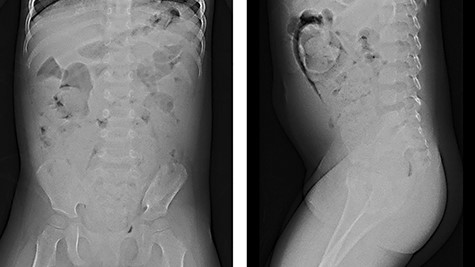

We report herein a case of a 4-year-old girl with ultrashort-segment HD (USHD). She was born at 29 weeks gestation from a twin pregnancy. Her birth weight was 1013 g. After birth, she was administered glycerin enemas to facilitate defecation. Thereafter, she was medicated with sodium picosulfate hydrate for chronic constipation, but she passed stool once in 4–5 days. When she was 4 years old, she was medicated with polyethylene glycol electrolyte solution (MOVICOL® [macrogol 4000]; EA Pharma Co., Ltd, Tokyo, Japan) in another hospital for chronic constipation. After she drank the MOVICOL® twice, her abdomen distended rapidly without passing stool, and she was transported to a hospital. An abdominal X-ray showed a stored stool mass (Fig. 1). A barium enema study revealed dilatation from the rectum to the sigmoid colon due to the stool mass and the rectum was smooth with funnel-shaped tapering toward the anus when she forced herself to defecate (Fig. 2). USHD was suspected, so she underwent anorectal manometry, which showed negative normal reflux. A surgical rectal full-thickness biopsy was performed 2 cm proximal to the dentate line under general anesthesia, which revealed very few ganglion cells in Auerbach’s plexus (Fig. 3a–c). She was suspected to have HD and underwent a Soave endorectal pull-through with an oblique anastomosis, where the pulled-through bowel was anastomosed posteriorly 0.5 cm from the dentate line, laterally 1.0 cm from the dentate line and anteriorly 1.5 cm above this point (Fig. 4). The posterior wall of the aganglionic anorectum was split longitudinally to the level of the dentate line. The resected specimen showed sparse ganglion cells with small cytoplasm in Auerbach’s plexus of the mucosectomy in the rectum (Fig. 5 ①, a and b). In the sigmoid colon of the resected specimen, most of the ganglion cells had scanty cytoplasm, whereas occasional ganglion cells with abundant cytoplasm were visualized (Fig. 5 ②, c and d). She passed stool 4–10 times a day for 6 months postoperatively, but the frequency of passing stool gradually deceased to once or twice a day without anastomotic strictures. Defecation was controlled without medications for 12 months postoperatively.

Barium enema: barium enema revealed dilatation from the rectum to the sigmoid colon due to a stool mass and the rectum showed a smooth funnel-shaped tapering toward the anus when she forced herself to defecate (black arrow: funnel-shaped tapering).